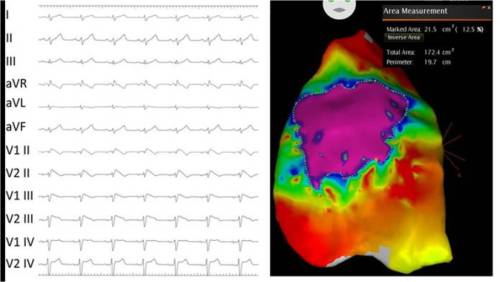

A 45 year old man came with recent onset breathlessness.His left ventricle was dilated along with left atrial enlargement.The LV EF was 42% (By current definition mid range preserved systolic function( Circ Heart Fail. 2016 Apr;9(4))

But, he was severely symptomatic because of combined systolic and diastolic dysfunction.Diagnosing and grading diastolic dysfunction has been extensively done in last decade.Now , we realise without significant diastolic dysfunction symptoms of pulmonary congestion can never occur in patients with DCM.

We don’t require complex tissue Doppler parameters to diagnose high-grade LV diastolic function.Just have a look at LA dimension, concentrate the E to A ratio. A tall E that humbles the A by more than 2 to 3 times is clear evidence for LA mean Pressure exceed 18 to 20 mmhg or so.

This , in combination with dilated LA is a marker of chronic severe diastolic dysfunction.The fact that A is diminutive in no way takes the Importance of Atrial contribution to LV filing at this critically compromised LV status.

Note E:A ratio is 3:1 .This simply means the early (and mid to a certain extent ) diastolic pressure in LA is high and most of the filling takes place before Atrial contraction .There is one more reason for diminutive A . Atrial contractility fails to prevail over E in late diastole as LV end diastolic pressure is significantly high in these patients with diastolic dysfunction.

A dilated left atrium is an Independent marker of significant LV diastolic dysfunction (In the absence of MR) .When does LA begin to enlarge in diastolic dysfunction ? There is uniform rule.Generally LA size more than 4.5cm indicate grade 3 or 4 LV diastolic dysfunction.